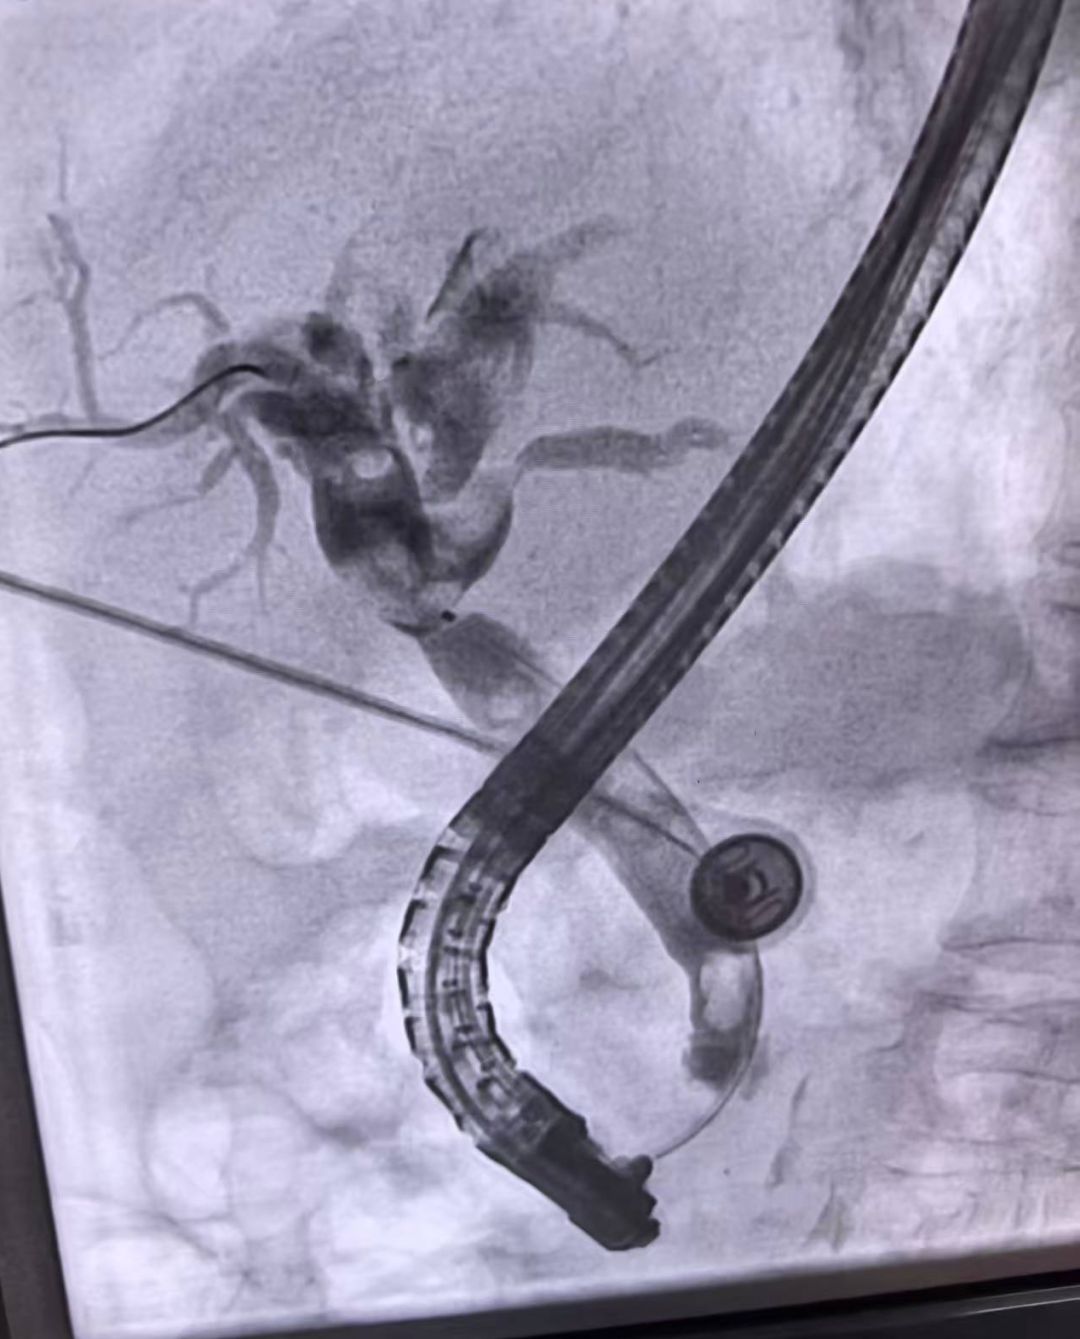

近日,在消化内科二病区,80岁的戚奶奶(化名)因胆道梗阻引发食欲不振、尿黄,生命健康亮起红灯,消化内科团队凭借精湛的ERCP(经内镜逆行胰胆管造影)技术,成功解除了危机,也再次印证了科室在高龄患者内镜治疗领域的过硬实力。

患者入院后,消化内科二病区主任成波立即组织团队进行病例讨论,最终决定采用ERCP技术为其实施微创治疗,最大程度降低手术创伤,更适合高龄患者。